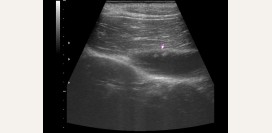

Ультразвуковое исследование (УЗИ)

Позволяет определить форму и наличие врожденных аномалий развития желчного пузыря, а также степень его опорожнения.

- Увеличение в размерах желчного пузыря свидетельствует о застое желчи — гипотоническая дискинезия.

- Уменьшение в размерах желчного пузыря — признак чрезмерного его сокращения (гипертоническая форма) либо врожденное недоразвитие (гипоплазия).

- Утолщение его стенок — острый холецистит или хронический холецистит в стадии обострения.

- Подвижные очаговые образования внутри желчного пузыря — камни.

- Неподвижные очаговые образования — камень, застрявший в желчном протоке либо сфинктере Люткенса-Мартынова.

- Очаговые образования, спаянные со стенкой желчного пузыря — застой желчи (холестаз) или опухоль.

- Расширение (дилатация) общего желчного протока — дискинезия желчевыводящих путей.

- Наличие осадка на дне желчного пузыря — гипомоторная дискинезия.

- Проведение диагностических проб для оценки способности сокращаться желчного пузыря с Сорбитолом, Магнием сульфатом, яичными желтками. При повышенной сократимости — гипермотроная дискинезия, при пониженной — гипомоторная форма заболевания.